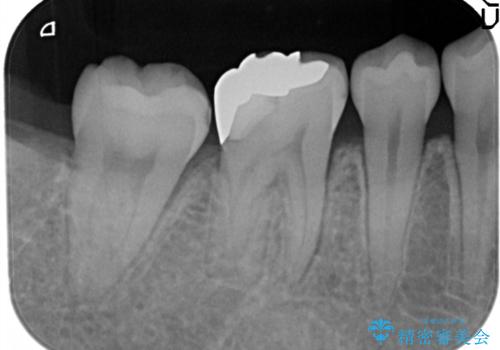

奥歯が痛い。根管治療~オールセラミッククラウン

- 奥歯の痛みを主訴に来院されました。

検査の結果、神経は保存不可能と診断されたため、根管治療~オールセラミッククラウンによる治療を行いました。

根管治療を行った歯は破折のリスクが高まるので被せものによる修復が必要になります。